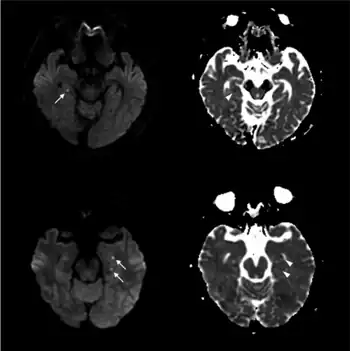

| Abnormal hippocampus findings consistent with transient global amnesia on MRI | |

Recently, moreover, both imaging and neurocognitive testing studies question whether TGA is as benign as has been thought. MRI scans of the brain in one study showed that among people who had experienced TGA, all had cavities in the hippocampus, and these cavities were far more numerous, larger, and more suggestive of pathological damage than in either healthy controls or a large control group of people with tumor or stroke.[15] Verbal and cognitive impairments have been observed days after TGA attacks, of such severity that the researchers estimated the effects would be unlikely to resolve within a short time frame.[16] A large neurocognitive study of patients more than a year after their attack has shown persistent effects consistent with amnestic mild cognitive impairment (MCI-a) in a third of the people who had experienced TGA.[37] In another study, "selective cognitive dysfunctions after the clinical recovery" were observed, suggesting a prefrontal impairment.[13] These dysfunctions may not be in memory per se but in retrieval, in which speed of access is part of the problem among people who have had TGA and experience ongoing memory problems.[12]